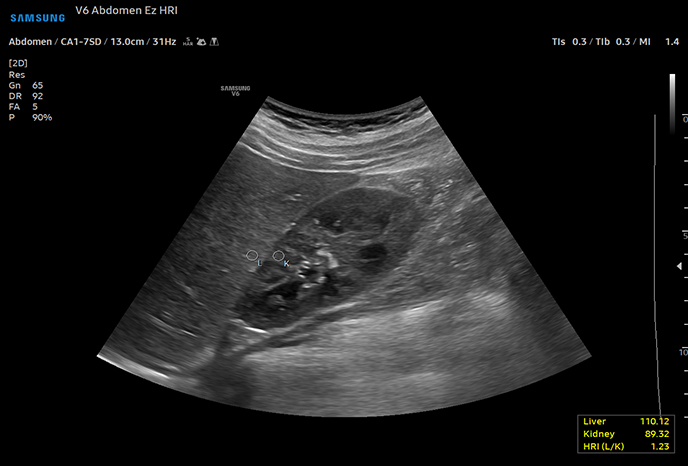

복부간담도계, 비장, 소화기계, 비뇨기계, 부신, 생식기계, 복강 림프절

S-디텍트